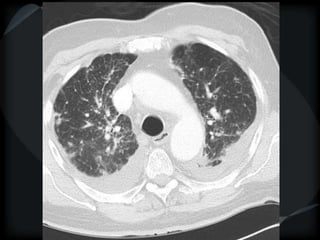

HRCT - Nodular Pattern

BRONCHIOLAR

 Centrilobular nodules: small airways of secondary lobule

 1-3mm away from pleura

 Not sub pleural

 Not on fissures or septae

Tree-in-Bud Appearance

Bronchiolitis

Rare- tumor cell emboli – intralobular artery

Bronchiolitis - MTB